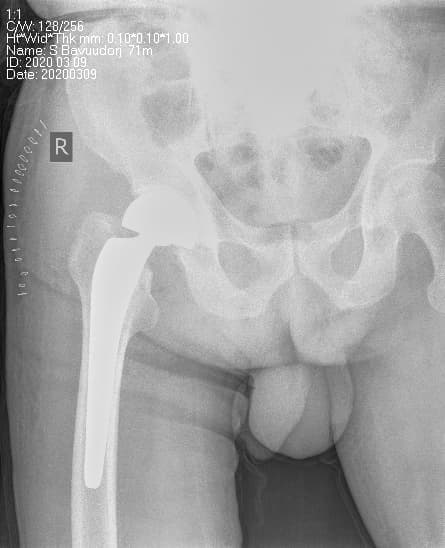

Мэс заслын өмнөх болон дараах рентген зураг

Түнхний үе солих мэс засал гэж юу вэ image4Түнхний үе солих мэс засал гэж юу вэ image5

Түнхний үе солих мэс засал гэж юу вэ image6Түнхний үе солих мэс засал гэж юу вэ image7